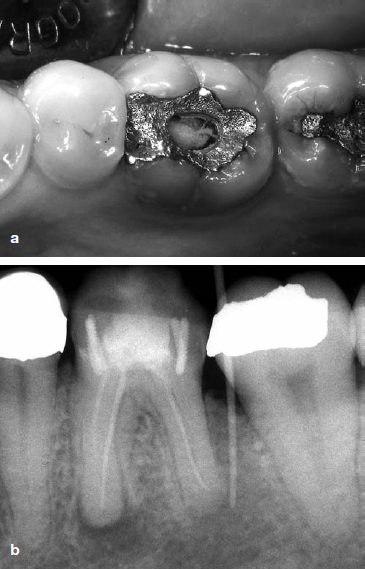

Fig 3. Apical periodontitis may continue for many years without symptoms. Main radiograph shows lower right molar which had received endodontic treatment 15 years ago. Inset shows same tooth 10 years prior to main radiograph. The unsatisfactory root canal treatment should have been re-done before the tooth was utilized as a bridge abutment.

Persistent endodontic disease, or apical periodontitis associated with a root-filled tooth, can continue for many years and may become apparent only when a tooth requires a new restoration or is detected on a routine radiograph (Fig 3). The fact that some microorganisms are capable of survival under harsh, nutrient-limited conditions of the root-filled canal for so long is remarkable. Yet, little information was known about the micro-organisms involved in persistent intra-canal infection after root filling until 1998, when two studies revealed that the microbial flora associated with persistent endodontic disease is quite unlike that found in other oral infections, or that of the untreated root canal.51,52